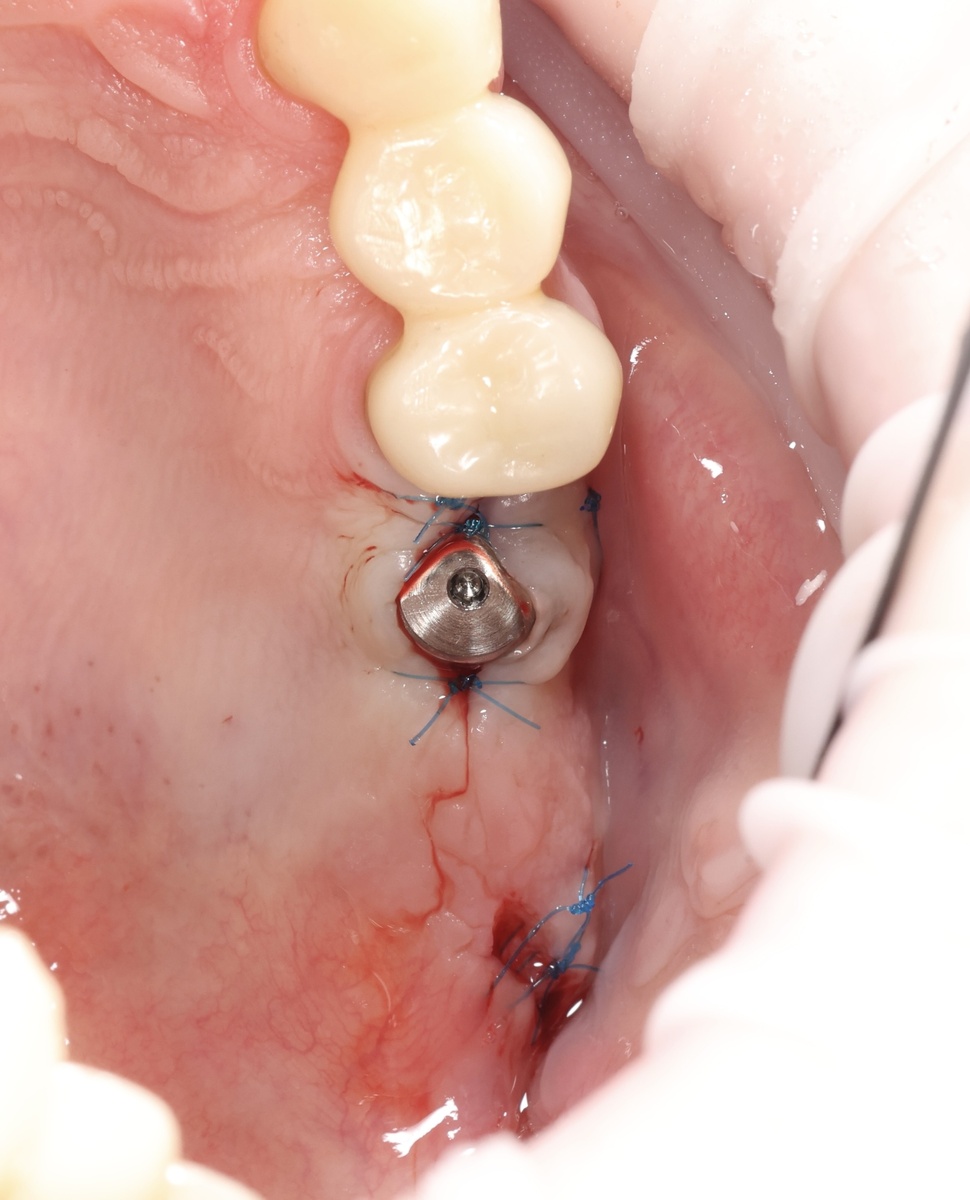

Март 2025 - имплантация зуба-антагониста на нижней челюсти с пластикой десны

Верхняя шестёрка будет, а жевать-то не получится адекватно. Нужен антагонист, зуб на челюсти нижней.

В марте установили имплант на позицию 3.6, нижняя шестёрка слева. С пластикой десны, чтобы вокруг импланта была нормальная прикреплённая слизистая. Покажу КТ в день имплантации выполненное:

Имплантат в области 3.6